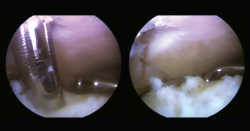

Se presenta el caso de un paciente varón de 54 años de edad, de profesión repartidor, que refiere una caída desde la plataforma de un camión, con torsión del tobillo derecho. Acude deambulando con la ayuda de un bastón. A la exploración física del tobillo derecho, presenta un balance articular disminuido con respecto al contralateral. Muestra dolor difuso a la palpación del ligamento peroneoastragalino anterior y posterior, y en la cúpula astragalina en la cara anterior del tobillo. No presenta dolor a la compresión de la sindesmosis. No da impresión de inestabilidad con maniobras de varo/valgo. En la radiografía se descartan fractura o signos indirectos de lesiones de partes blandas (Figura 1).

Figura 1. Radiografía anteroposterior y lateral del tobillo derecho.